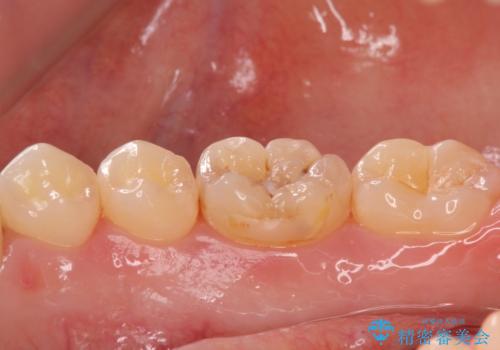

矯正後の虫歯治療 セラミックインレーでの治療

- 矯正後の虫歯治療です。

咬む面と歯と歯の間の虫歯に対してセラミックインレーでの修復処置をしていきます。

- 右下6 セラミックインレー 77,000円費用は治療当時の料金となります

下の奥歯は外から見える場所です。審美的なセラミックでの治療をおすすめします。